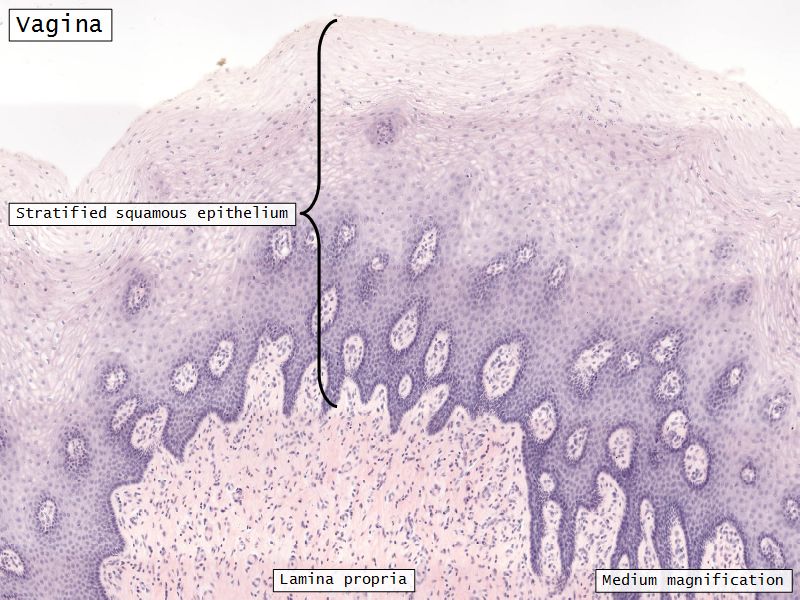

Mucosa

- Epithelium

- Thick stratified squamous nonkeratinized

- Lamina propria

- Fibroelastic connective tissue

- Rich in elastic fibres

- Contains lymphoid elements

- Deep portion highly vascular

- No glands